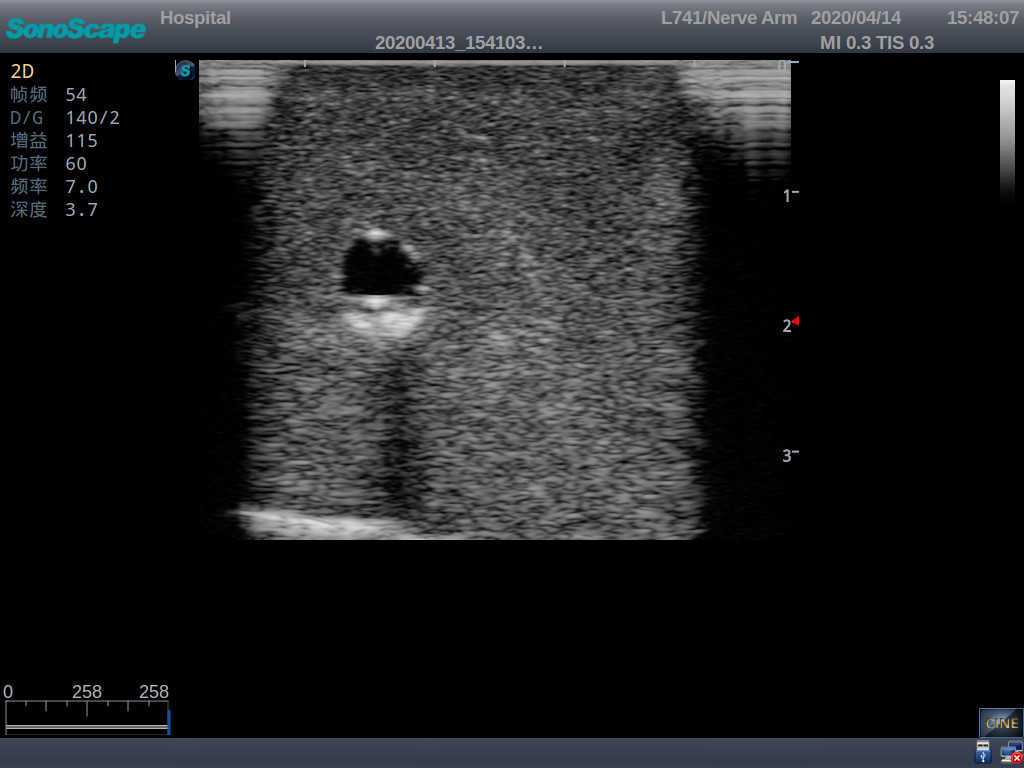

Model TYE1510.1

Product size(mm) 700×500×160

It is a model covering up from lobulus auriculae plane to the umbilical plane, and it has anatomical structures like clavicle, rib, sternocleidomastoid, jugular vein and basilic vein.

1)   Made of high molecular polymer ultrasound material, close to the real skin

2)   It can be used by real ultrasound machines

3)   Clear and real images of the tissues and organs (basilic vein and superior vena cava)